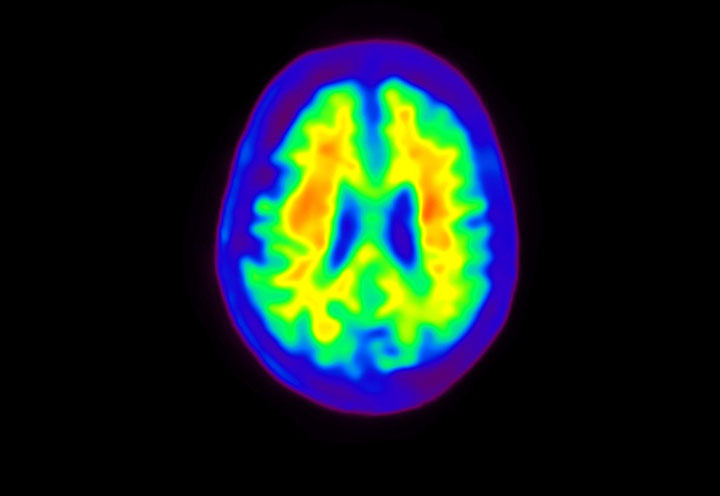

Head / Case4 : Amyloid

Sagittal

Courtesy : Kindai University Hospital

- Imaging protocol

- Injected dose: 3.21 MBq/kg, 18F-Flutemetamol

- Uptake time: 100 minutes

- Scan time: 20 minutes